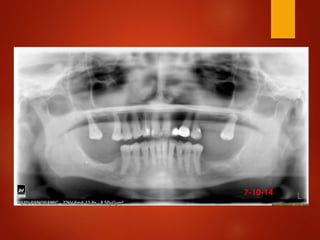

El documento es un registro médico odontológico que muestra las fechas de las visitas de un paciente al centro de salud El Raval, incluyendo exámenes y tratamientos realizados como la extracción de cálculos salivales en abril y mayo de 2012.